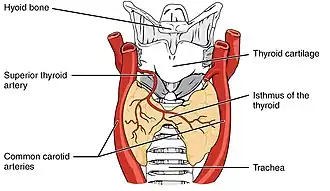

The human thyroid (tan), as viewed from the front; and arteries (red) supplying the gland. | |

The thyroid, or thyroid gland, is an endocrine gland in vertebrates. In humans, it is a butterfly-shaped gland located in the neck below the Adam's apple. It consists of two connected lobes. The lower two thirds of the lobes are connected by a thin band of tissue called the isthmus (pl.: isthmi). Microscopically, the functional unit of the thyroid gland is the spherical thyroid follicle, lined with follicular cells (thyrocytes), and occasional parafollicular cells that surround a lumen containing colloid.

The thyroid gland is a butterfly-shaped organ composed of two lobes, left and right, connected by a narrow tissue band, called an "isthmus".[4] It weighs 25 grams in adults, with each lobe being about 5 cm long, 3 cm wide, and 2 cm thick and the isthmus about 1.25 cm in height and width.[4] The gland is usually larger in women than in men, and increases in size during pregnancy.[4][5]

The thyroid is near the front of the neck, lying against and around the front of the larynx and trachea.[4] The thyroid cartilage and cricoid cartilage lie just above the gland, below the Adam's apple. The isthmus extends from the second to third rings of the trachea, with the uppermost part of the lobes extending to the thyroid cartilage and the lowermost around the fourth to sixth tracheal rings.[6] The infrahyoid muscles lie in front of the gland and the sternocleidomastoid muscle to the side.[7] Behind the outer wings of the thyroid lie the two carotid arteries. The trachea, larynx, lower pharynx and esophagus all lie behind the thyroid.[5] In this region, the recurrent laryngeal nerve[8] and the inferior thyroid artery pass next to or in the ligament.[9] Typically, four parathyroid glands, two on each side, lie on each side between the two layers of the thyroid capsule, at the back of the thyroid lobes.[4]

Blood, lymph and nerve supply

The thyroid is supplied with arterial blood from the superior thyroid artery, a branch of the external carotid artery, and the inferior thyroid artery, a branch of the thyrocervical trunk, and sometimes by an anatomical variant the thyroid ima artery,[4] which has a variable origin.[10] The superior thyroid artery splits into anterior and posterior branches supplying the thyroid, and the inferior thyroid artery splits into superior and inferior branches.[4] The superior and inferior thyroid arteries join behind the outer part of the thyroid lobes.[10] The venous blood is drained via superior and middle thyroid veins, which drain to the internal jugular vein, and via the inferior thyroid veins. The inferior thyroid veins originate in a network of veins and drain into the left and right brachiocephalic veins.[4] Both arteries and veins form a plexus between the two layers of the capsule of the thyroid gland.[10]